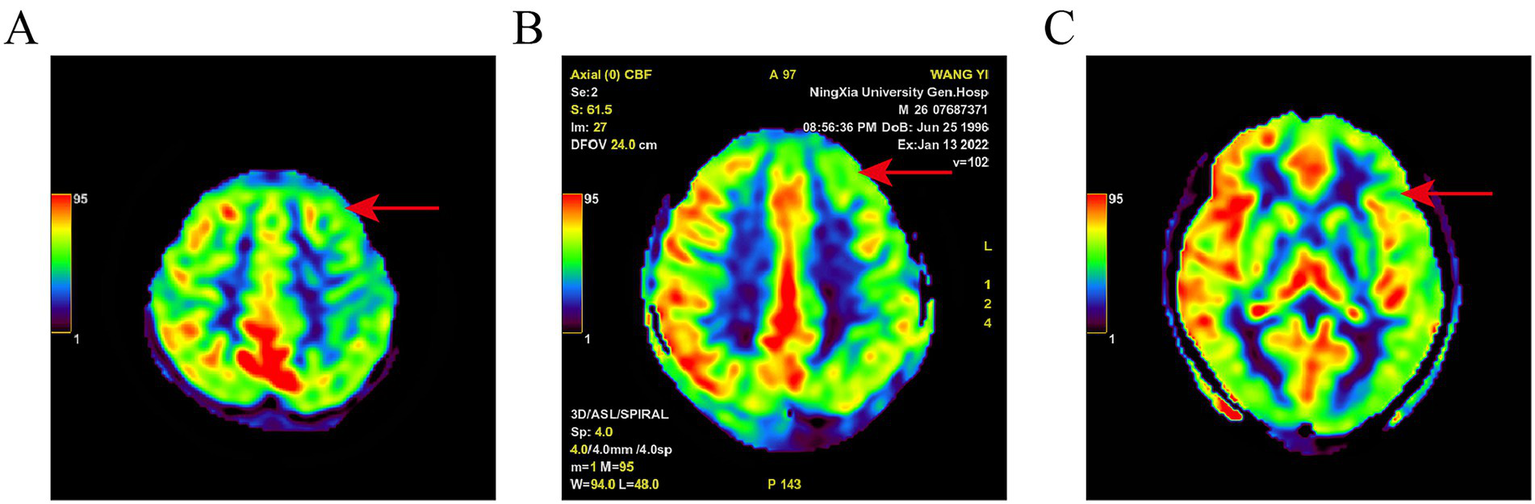

The positive result for SPECT/CT were reduced rCBF (Figure 1). The positive result for AEEG were the detection of IEDs. The positive result for 3D-pCASL were either reduced rCBF, increased rCBF, or coexisting increased and reduced rCBF (Figure 2). The positive detection rates for SPECT/CT, AEEG, and 3D-pCASL examinations were 77.55% (76/98), 62.24% (61/98), and 54.08% (53/98) respectively.

Figure 2

Pseudo-color map of ASL in a PWE. Different color bands and values in the upper left corner represent CBF from low to high; (A): left frontal lobe hypoperfusion; (B): left frontal lobe hypoperfusion; (C): left temporal lobe hypoperfusion. Red arrow indicates ischemic lesion.